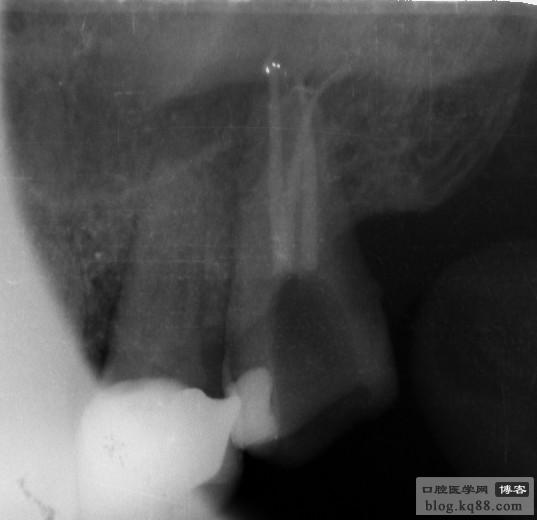

上頜中切牙及側(cè)切牙

左上中切牙

右下5

右上5、6

右下6

左上6

右下8

右上8